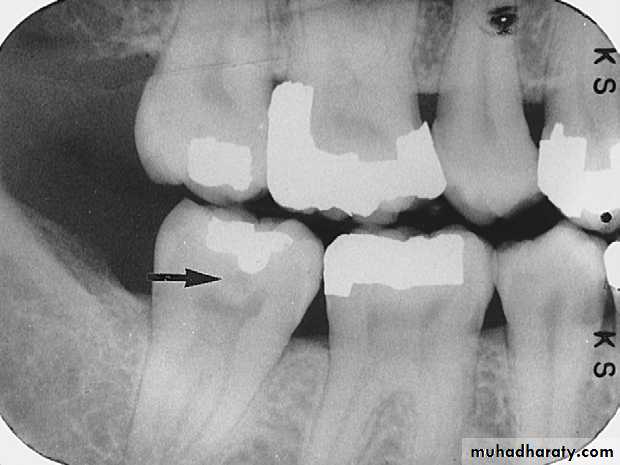

Recurrent Caries

Recurrent caries seen as a radiolucency below a two surface amalgam restoration on the mandibular second premolar.

Recurrent caries on upper first premolar